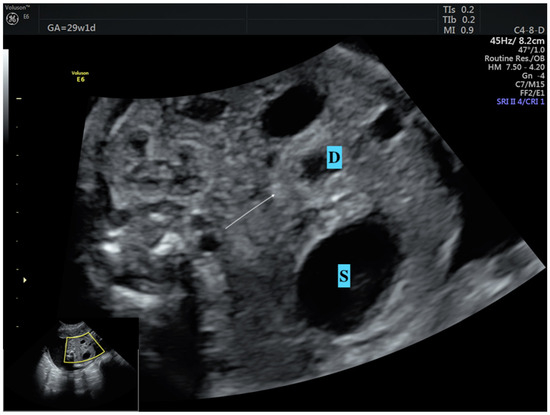

- Dankovcik, R.; Jirasek, J.E.; Kucera, E.; Feyereisl, J.; Radonak, J.; Dudas, M. Prenatal diagnosis of annular pancreas: Reliability of the double bubble sign with periduodenal hyperechogenic band. Fetal Diagn. Ther. 2009, 24, 483–490. [Google Scholar] [CrossRef] [PubMed]

- Yin, C.; Tong, L.; Ma, M.; Tan, X.; Luo, G.; Fei, Z.; Nie, D. The application of prenatal ultrasound in the diagnosis of congenital duodenal obstruction. BMC Pregnancy Childbirth 2020, 20, 387. [Google Scholar] [CrossRef]

- Zhang, B.; Zhang, W.; Hu, Y.; Pang, H.; Yang, H.; Luo, H. Evaluation of prenatal and postnatal ultrasonography for the diagnosis of fetal double bubble sign. Quant. Imaging Med. Surg. 2024, 14, 6386. [Google Scholar] [CrossRef]

- Demirci, O.; Eriç Özdemir, M.; Kumru, P.; Celayir, A. Clinical significance of prenatal double bubble sign on perinatal outcome and literature review. J. Matern.-Fetal Neonatal Med. 2022, 35, 1841–1847. [Google Scholar] [CrossRef] [PubMed]

| Double bubble sign (n, %) | 13 (100) | 17 (100) | N/A |

| Dilated stomach (n, %) | 13 (100) | 17 (100) | N/A |